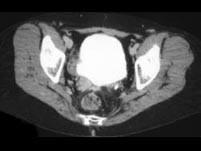

男,56岁,请根据所示图像,选择最可能诊断 ( )A、右侧输尿管乳头状瘤B、右侧输尿管癌C、膀胱结核D、右侧输尿管结核E、膀胱癌

问题 男,56岁,请根据所示图像,选择最可能诊断 ( )

选项 A、右侧输尿管乳头状瘤 B、右侧输尿管癌 C、膀胱结核 D、右侧输尿管结核 E、膀胱癌

答案 B